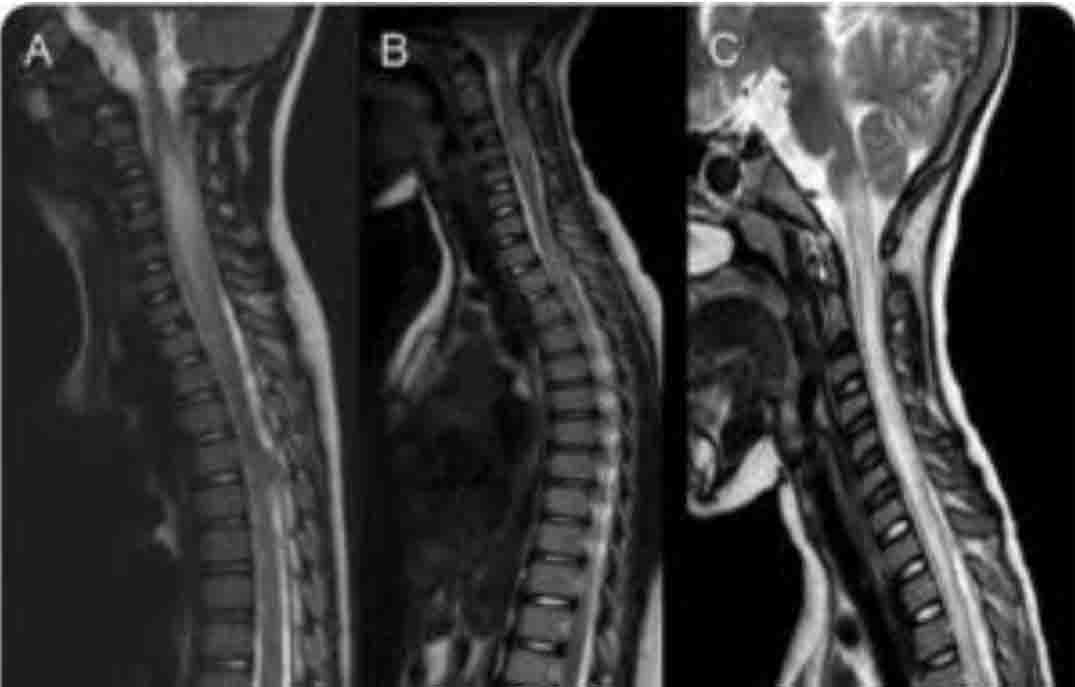

مطالعه جدیدی که در مجله Children منتشر شده است ، نشان می دهد که ترکیبی از تحریک نخاعی از طریق پوست (TSS) و تمرین حرکتی می تواند به کودکان مبتلا به AFM کمک کند تا توانایی راه رفتن خود را بهبود بخشند. TSS یک روش درمانی غیر تهاجمی است که در آن جریان الکتریکی از طریق پدهایی که روی پوست قرار میگیرند تا ستون فقرات اعمال میشود. حجم سیگنالهایی را که از مغز از طریق نخاع عبور میکنند، تقویت میکند و باعث تسهیل فعالسازی عضلات و بازیابی عملکرد حرکتی میشود.

این مطالعه شامل چهار کودک مبتلا به آسیب نخاعی ناشی از AFM بود. طی یک سری 22 جلسه درمانی ، بیماران در حالی که روی تردمیل حرکت می کردند، TSS دریافت کردند، زیرا بخشی از وزن بدن آنها توسط یک سیستم مهار پشتیبانی می شد. نتایج امیدوارکننده بود – سه کودک در مسافت پیادهروی بهبودهایی نشان دادند و دو کودک در وضعیت بدنی، سرعت و عملکرد کلی راه رفتن پیشرفتهای قابلتوجهی داشتند.